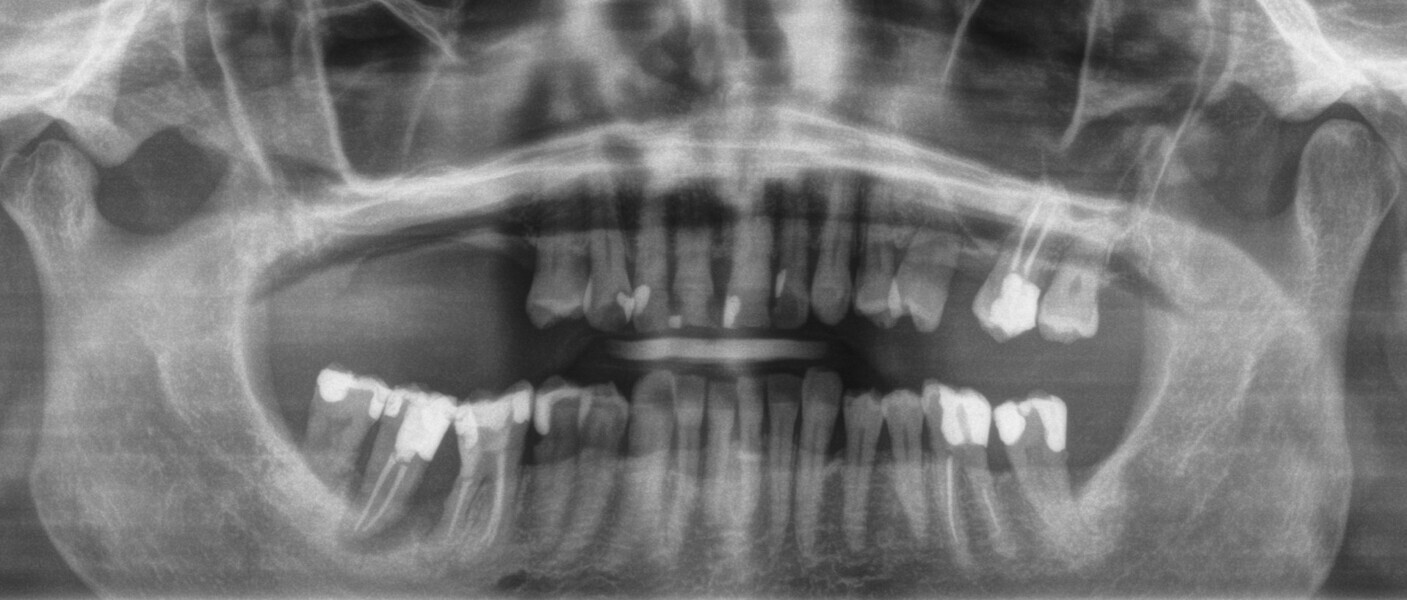

A 62-year-old female patient (ASA Class I), a non-smoker and with normal glucose levels, with previously treated periodontal disease presented for implant and prosthetic rehabilitation of the upper jaw (Fig. 1). Radiographic analysis, performed through a dental panoramic tomogram and CBCT scan, revealed the presence of a vertical bone defect in the right posterior sextant, due to the complete loss of the alveolar process (Figs. 2; 3a & b). The clinical examination showed the severity of the bone defect, which had resulted in an obvious volume deficiency in both the horizontal and vertical dimensions (Figs. 4 & 5).